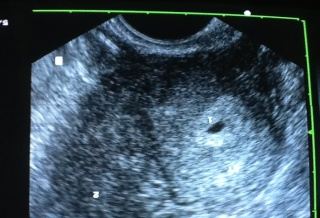

(優活健康網記者杜宇喬/綜合報導)許多人不知道,試管嬰兒的過程相當繁複且辛苦,一位新北市患有不孕症婦人,曾經在許多醫院做過5次試管嬰兒胚胎都是植左邊子宮都失敗,醫師檢查後發現她有左右兩個子宮,類似上下鋪的結構,這名婦人案例不多見,婦產科醫師蔡鋒博評估這名婦人的情形之後,決定將各放2個胚胎在2個子宮果真使婦人懷上了兩邊子宮各懷一個胚胎,生下胞胎,連醫師也對於成果十分驚訝。

蔡鋒博表示,婦人上面的陰道通往左邊子宮下面陰道通往右邊子宮,醫師評估後建議,若要做試管嬰兒時最好把胚胎放在右邊子宮,比較有機會著床,但是婦人和她的丈夫堅持決定要把4個胚胎分成左右各放2個在兩個子宮,由於婦人年紀的因素符合放4個胚胎的適應症,植入培育後,過程中也相當順利。病人在驗孕前5天覺得肚子發脹,醫師一聽症狀,趕快叫她來抽血,證實她已經懷了胞胎。

醫師表示,這實在是非常少見,更少見的是大部份的陰道通常是左右,好像馬路的安全島分開左右兩邊,而她的陰道卻是上下鋪,但是她的子宮是左右分兩邊,實在是不曉得她的子宮子宮頸跟陰道是怎麼扭轉的,扭轉成左右的子宮,陰道是上下鋪,而且做試管嬰兒左右子宮各懷一個胚胎,實屬罕見更是試管嬰兒案例中相當少見的例子。